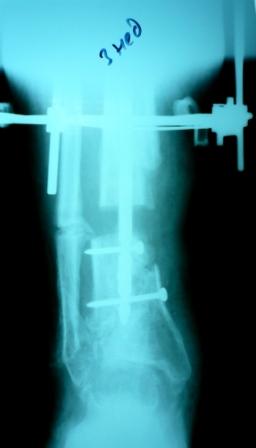

2)  После репозиции более очевидна стала проблема дефекта кости в верхней трети голени, два фрагмента свободно лежат. Остановились на варианте перехода на интрамедуллярный синтез стержнем с покрытием костный цемент+ванкомимцин и замещении дефекта с помощью транспорта фрагмента (рис 2)

Имя     : Рис 2 после операции 27.02.09.JPG

Тип     : image/jpeg

Размер  : 14504 байтов

Описание: отсутствует

Url     : http://weborto.net:8080/pipermail/ortho/attachments/20090405/a3dc024e/attachment-0013.jpeg

Имя     : Рис 2 после операции 27.02.09 (1).JPG

Размер  : 14471 байтов

Url     : http://weborto.net:8080/pipermail/ortho/attachments/20090405/a3dc024e/attachment-0014.jpeg